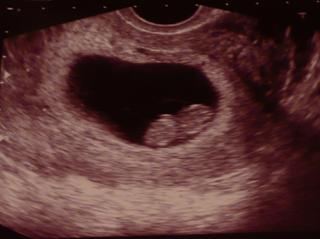

Ahojky, taky se chci přidat, už jsem vám sem psala v únoru, jak jsem hned našla // a teď hlásím, že jdu v pondělí 12.3. poprvé na kontrolu, celá se třesu. Měla bych být dnes dle poslední MS 8+3, ale bude to asi menší, jelikož mám cykly tak 32d i více. Tak mi držte pěstičky, čekám třetí a je mi čerstvě 42let.